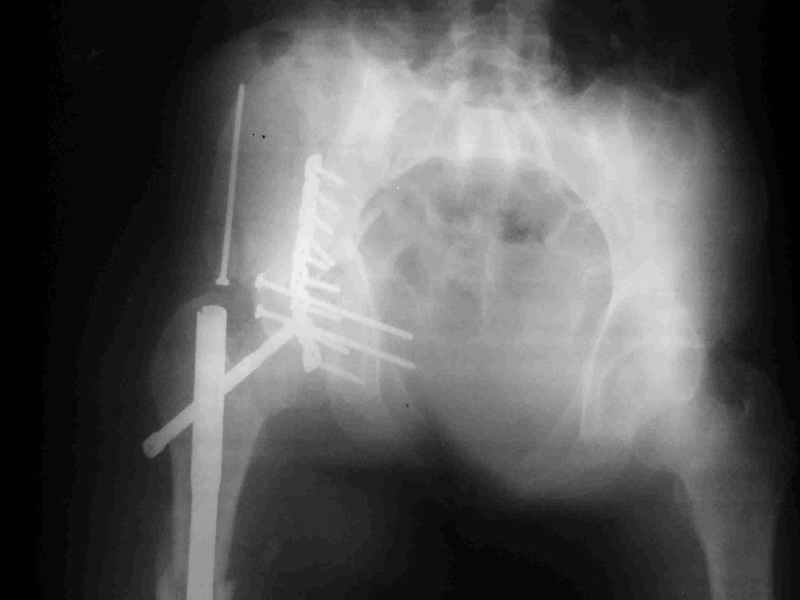

Еще раз спасибо за комментарии и готовность помочь с имплантами. Постоп картинки в приложении,

Не дождавшись советов, в понедельник прооперировал больного, заняло времени..., но все сделал в один этап: сначала фиксировал ипсилатеральный перелом бедра и шейки реконструктивным гвоздем Smith&Nephews, потом из расширенного илеофеморального доступа фиксировал перелом крыла подвздошной кости тягловым винтом, нейтрализующей пластиной заднюю колонну, и тягловыми винтами 3,5 мм переднюю колонну.

К сожалению, набора для ретроградного или антеградного реконструктивного штифтования в операционной нет, поэтому доставка заняла н-ное время. Вопрос, который возник у меня- по поводу оптимальной тактики хирургии: вся фиксация в один этап из расширенного доступа или последовательно сначала бедро и позже реконструкция впадины, комбинированный доступ к впадине отдельно к передней и задней колоннам или из расширенного илеофеморального одного доступа. Все-таки решил остановиться на одноэтапном подходе и спустя 5 дней (как раз и наборы привезли) из расширенного илеофеморального доступа сначала фиксировал реконструктивным штифтом Smith&Nephews бедро и

шейку (благо перелом шейки 2 типа -относительно стабильный) затем фрагмент крыла подвздошной кости Lag screw, далее пластина на заднюю колонну и винты в переднюю колонну.(с размерами и направлением винтов ошибка вышла:-((, но интраоперационно у меня была полная уверенность , что винты *ушли* в лонную кость).